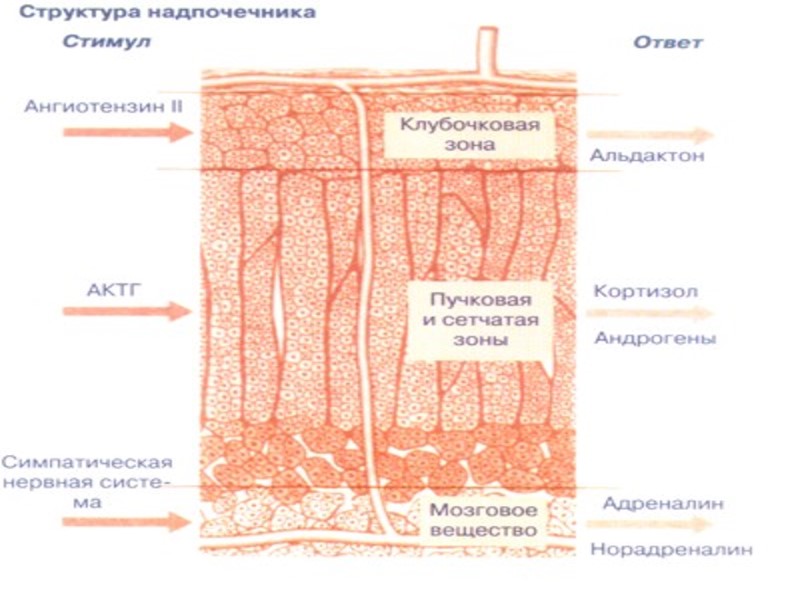

Эффекты глюкокортикостероидов Углеводный обмен: стимуляция глюконеогенеза и гликогенолиза; Липидный обмен: ускорение липолиза в конечностях и ускорение липогенеза на лице и туловище; Белковый обмен: анаболическое действие в печени и катаболическое в других органах; Иммунная система: иммунодепрессанты в высоких дозах; Воспаление: выраженный противовоспалительный эффект; Обмен натрия и калия: задерживают в организме натрий и способствуют выведению калия; Кроветворная система: стимуляция гранулоцитарного и эритроидного ростков гемопоэза …

Минералокортикоиды: функция – поддержание баланса электролитов и жидкости в организме; она осуществляется посредством влияния на реабсорбцию ионов в почечных канальцах при связывании с альдостероновыми рецепторами. - Натрий: увеличение реабсорбции → увеличение содержания жидкости в организме и повышение АД; - Калий: увеличение экскреции калия → гипокалийемия; - Cl-, HCO3-, H+, Mg2+, Ca2+ - увеличение реабсорбции хлора и бикарбоната и почечной экскреции ионов водорода

Андрогены (дегидроэпиандростерон, андростендион) – обладают анаболическим и гипохолестеринемическим эффектами. У мужчин играют незначительную роль в поддержании общей концентрации андрогенов в плазме

Катехоламины надпочечников (адреналин и норадреналин) – широкий спектр эффектов (воздействие на глкогенез, липолиз, глюконеогенез, ССС, НС, ДС …). Реализация функций осуществляется через α- и β-адренергические рецепторы на поверхности клеток-мишеней (ГМК, секреторный клетки, кардиомиоциты). Клинические проблемы возникают (в основном) при опухолях эндокринных клеток и их предшественников (феохромоцитома, нейробластома)